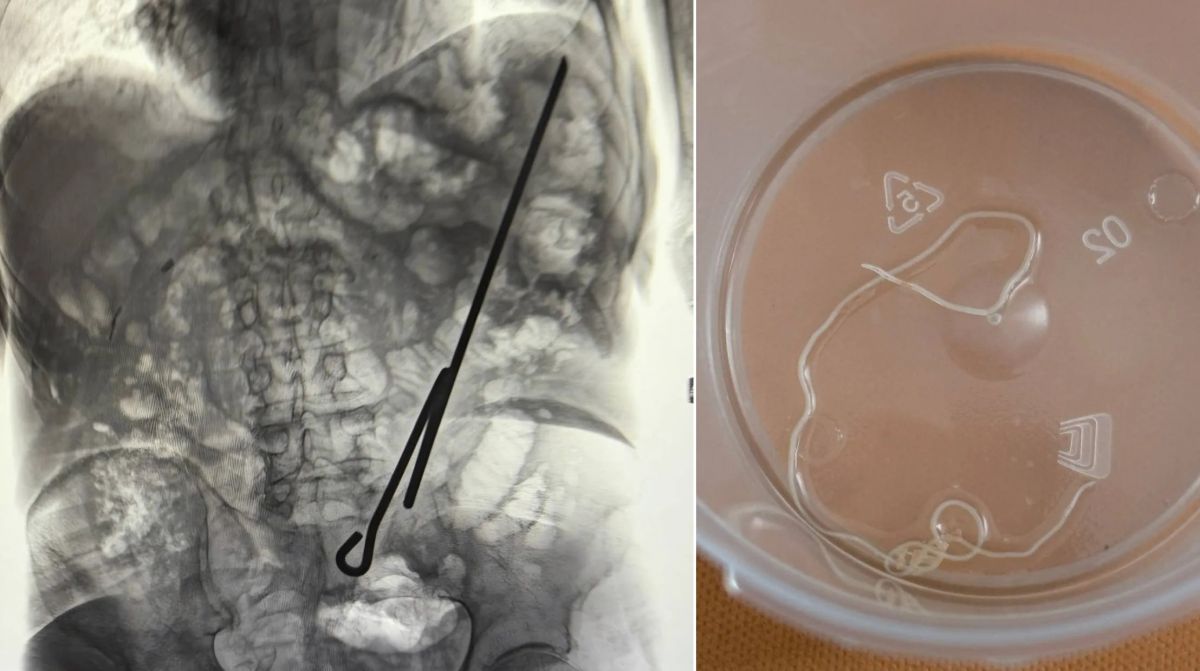

© Фото: "Воронежские новости"

Напомним, что очаг сибирской язвы обнаружили в Панинском районе Воронежской области. Мужчина заразился опасной инфекцией от коровы.

Известно, что сельчанин забил животное, а мясо реализовал. У мужчины осталась лишь шкура, на которой и обнаружили ДНК возбудителя болезни. Выяснилось, что воронежец не предоставлял ветеринару для осмотра корову и не делал ей вакцины.